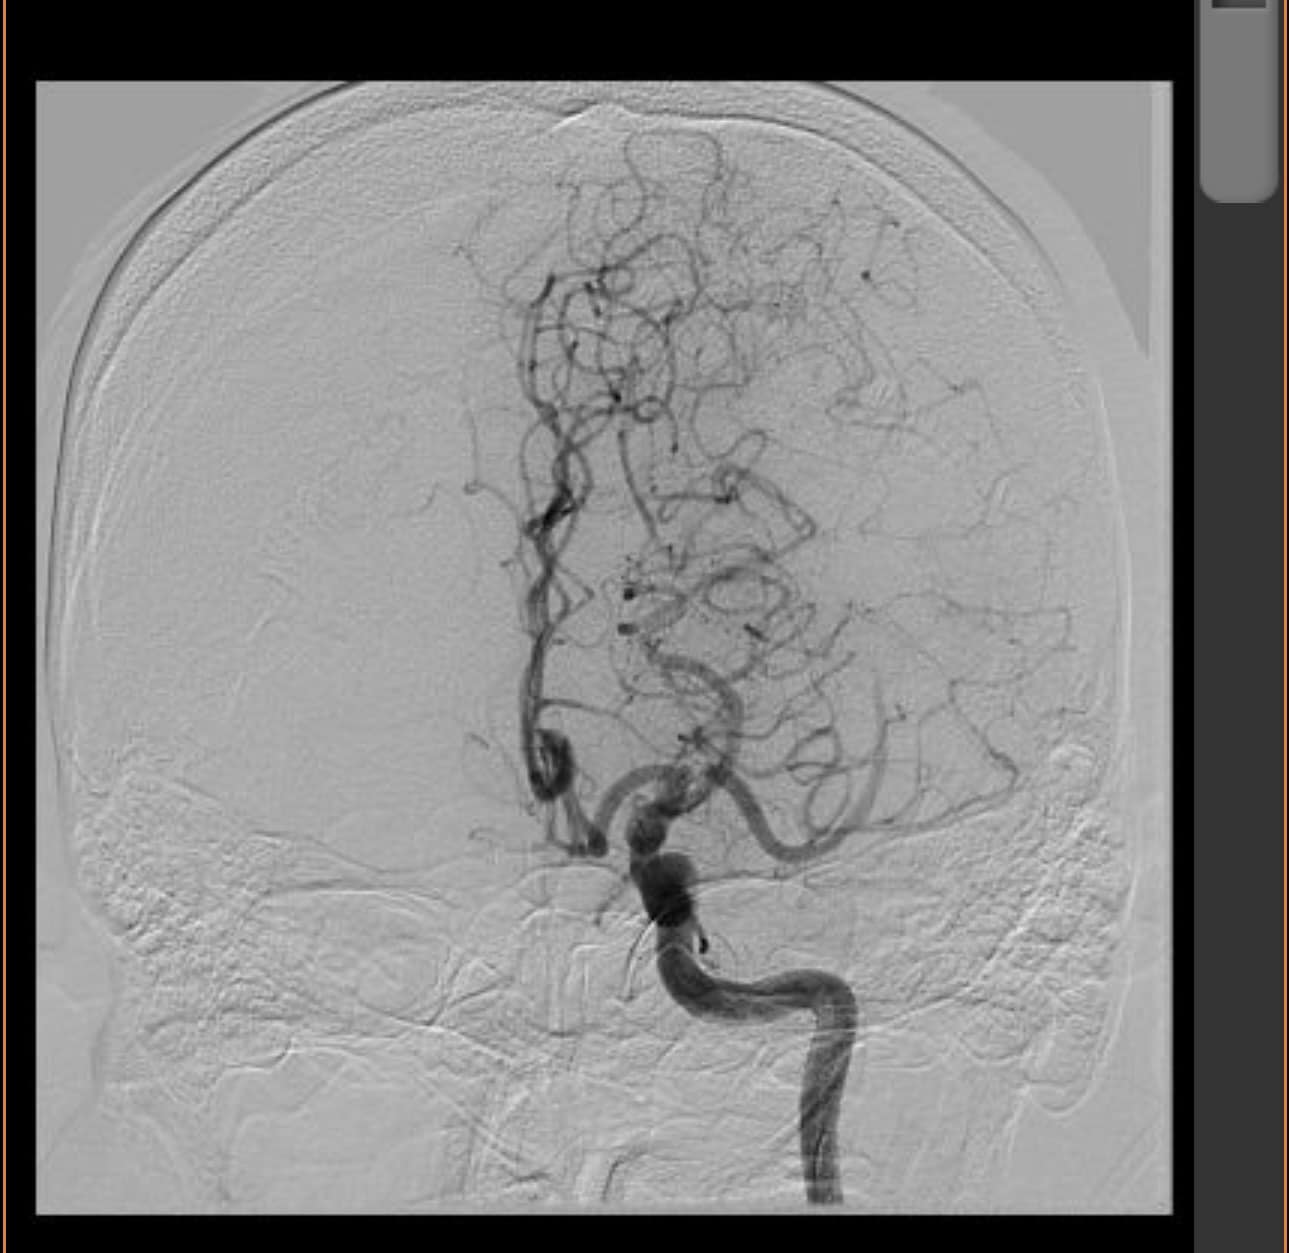

Trên trang cá nhân của mình PGS.TS.BS Nguyễn Huy Thắng – Chủ tịch Hội Đột quỵ TPHCM, Phó Chủ tịch Hội Đột quỵ Việt Nam chia sẻ, cách đây vài ngày, một chàng thanh niên 27 tuổi, nhập viện sau hơn 10 tiếng trong tình trạng nói khó, yếu nhẹ 1/2 người P. Trước đó, bệnh nhân có nhiều cơn TIA với biểu hiện tương tự. Trên phim chụp MRI ghi nhận nhồi máu nhỏ nhân đuôi T, kèm hẹp nặng/ hoặc tắc động mạch não giữa T. Bác sĩ điều trị chọn phác đồ kháng tiểu cầu kép và statin liều cao.

Ảnh chụp MRI não của nam bệnh nhân có biểu hiện đột quỵ nhẹ.

Khoảng 24 giờ sau khi nhập viện, các triệu chứng của nam bệnh nhân diễn tiến nặng, tay và chân liệt 0/5, mất ngôn ngữ toàn bộ. Bệnh nhân được chụp lại khẩn MRI kèm MRI perfusion. Hình ảnh lần 2 cho thấy thể tích nhồi máu đã lan rộng ở nhiều nơi thuộc chi phối bởi động mạch não giữa T.

Về trường hợp này, chuyên gia nhận định, đây là một tình huống lâm sàng rất khó để thầy thuốc đưa ra những lựa chọn phù hợp, khi chúng ta chưa có đủ các chứng cứ ủng hộ việc can thiệp xâm lấn trên những bệnh nhân đột quỵ nhẹ có kèm tắc động mạch não lớn.

Theo PGS.TS.BS Nguyễn Huy Thắng, những trường hợp đột quỵ nhẹ cho dù tắc động mạch não lớn thường có tuần hoàn phụ rất tốt, đặc biệt với những bệnh nhân hẹp động mạch trước đó. Việc can thiệp xâm lấn khi chưa cần thiết, có thể làm xấu thêm các triệu chứng, thậm chí tử vong. Hiện nay đang có 2 thử nghiệm lâm sàng RCT về vấn đề này. Hy vọng sẽ có câu trả lời trong 2 năm tới.

Hình ảnh perfusion có thể giúp ích trong một số trường hợp khi Tmax>6s volume lớn hơn 60ml (có giá trị tiên lượng mạnh tiến triển xấu của ổ nhồi máu). Lựa chọn thận trọng hơn, theo dõi sát các khiếm khuyết thần kinh, có thể cân nhắc can thiệp Rescue khi triệu chứng nặng lên dần.